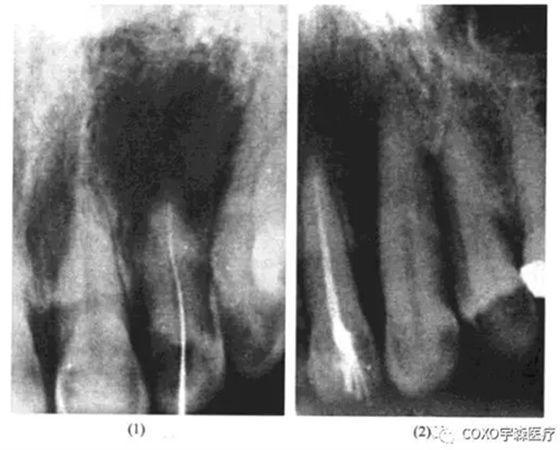

三、根尖周病與夜磨牙癥

病例 女性,20歲,因下前牙酸痛感,醫(yī)師為其攝片檢查示:1-1根尖區(qū)有透射陰影,范圍大不規(guī)則,認(rèn)為根尖區(qū)有病變,誤將1]開髓,發(fā)現(xiàn)為活髓,暫封,未預(yù)約處理,半年后再攝片檢查1],發(fā)現(xiàn)1]牙內(nèi)吸收,并導(dǎo)致牙根穿孔,而T一直存在活力,仔細(xì)詢問病史,患者有夜磨牙癥病史(圖13-6)

根尖周陰影,多數(shù)情況牙髓都已壞死,但是在確診之前,常規(guī)的牙髓活力測(cè)定是必需的。該牙無齲,無楔狀缺損,引起根尖區(qū)骨質(zhì)稀疏,尤其是下頜前牙,由于垂直方向受力,容易考慮到是咬合創(chuàng)傷,甚至是夜磨牙癥。雖然在處理的當(dāng)時(shí)1]還是活髓,最終仍有可能逆行性牙髓壞死。醫(yī)師未仔細(xì)詢問病史、作牙髓活力測(cè)定,就開髓,是工作不細(xì)致、不嚴(yán)謹(jǐn)、責(zé)任心不強(qiáng)的表現(xiàn)。

根尖周骨質(zhì)稀疏,又系活髓,應(yīng)詢問有無外傷史,夜磨牙病史,當(dāng)證癥,如能查出引起夜磨牙癥之病因,應(yīng)當(dāng)去除致病因素,并用給板再調(diào)給磨對(duì)根尖有病變的牙行根管治療術(shù)。四、根尖周病與腫瘤及類腫瘤疾病